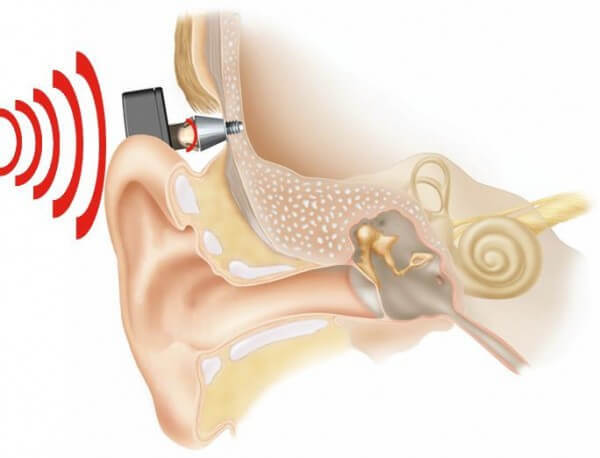

Современные слуховые аппараты при сенсоневральной тугоухости